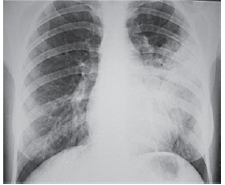

Mulher de 49 anos é internada devido dispneia, febre e dor torácica à esquerda iniciados há 3 dias. Pressão arterial: 110 x 60 mmHg, pulso: 115 bpm; temperatura: 38,3 ºC, frequência respiratória: 26 ipm e saturação arterial de oxigênio: 85%. Radiografia realizada é ilustrada a seguir.

Enunciado 3309351-1

Nesse momento, é correto afirmar: